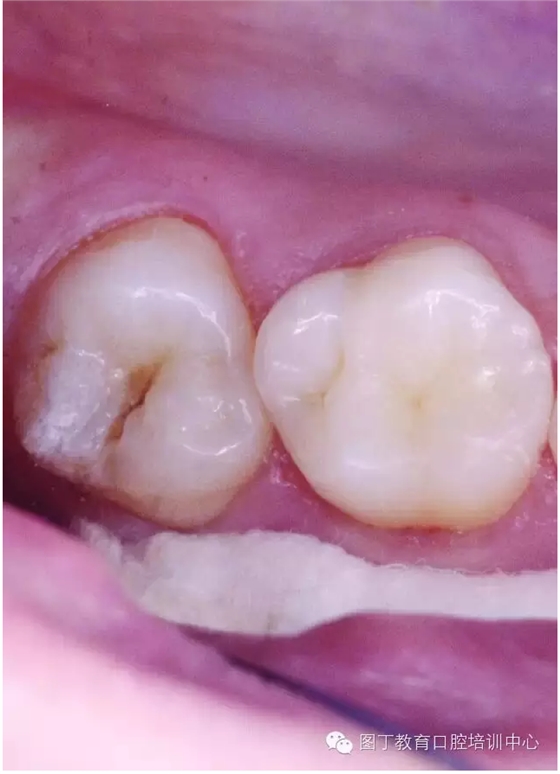

窩溝封閉前后

窩溝封閉前